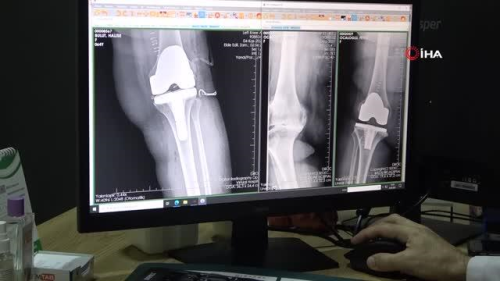

"İleri aşamalı eklem kireçlenmeleri ciddi sorunlara sebebiyet veriyor" Ortopedi ve Travmatoloji Uzmanı Doç. Dr. Bulut: "İleri aşamalı eklem kireçlenmelerinde kıkırdak tamamen yok olmakta ve kemikler birbirine sürtünmektedir, bu durum kendini hastalarda şiddetli ağrı, hareket kısıtlılığı ve şekil bozukluğu olarak göstermektedir" "Yaşlı nüfusun artmasıyla günümüzde eklem kireçlenmeleri oldukça sık görülmektedir" "Diz ve kalça, kireçlenmenin en sık görüldüğü iki eklemdir"

ELAZIĞ - Teknolojik gelişmeler, yaşam standartlarının yükselmesi, yaşlı nüfusu ile iş ve trafik kazalarının artmasıyla eklem kireçlenmelerinin daha sık görüldüğüne dikkat çeken Ortopedi ve Travmatoloji Uzmanı Doç. Dr. Mehmet Bulut, "Diz ve kalça, kireçlenmenin en sık görüldüğü iki eklemdir. Kireçlenmenin erken aşamasında kıkırdaklarda düzensizlik, saçaklanma ve çatlaklar meydana gelmektedir. Tedavisinde ise, hastaların kilo vermesi, egzersiz fizik tedavi ve ilaç kullanımı yer almaktadır" dedi. Elazığ Mediline Hastanesi Ortopedi ve Travmatoloji Uzmanı Doç. Dr. Mehmet Bulut, eklem kireçlenmesi, kireçlenmeye sebebiyet veren etkenler ve uygulanan yöntemler hakkında bilgi verdi. Doç. Dr. Mehmet Bulut yaptığı açıklamada, "Bir yandan teknolojinin gelişmesiyle birlikte araç, gereç ve makinaların artmasına bağlı olarak trafik ve iş kazalarının sık görülmesi diğer yandan toplumda beklenen yaşam süresinin uzaması nedeniyle yaşlı nüfusunun artmasıyla günümüzde eklem kireçlenmeleri oldukça sık görülmektedir. Eklem kireçlenmesinde, eklemi oluşturan en önemli yapılardan biri olan kıkırdakta aşınma ve harabiyet medyana gelmektedir. Diz ve kalça, kireçlenmenin en sık görüldüğü iki eklemdir. Kireçlenmenin erken aşamasında kıkırdaklarda düzensizlik, saçaklanma ve çatlaklar meydana gelmektedir. Bu erken ve orta aşamalı kireçlenmelerin tedavisinde, hastaların kilo vermesi, egzersiz fizik tedavi ve ilaç kullanımı yer almaktadır. Yine bu aşamada uyguladığımız diğer bir tedavi yöntemi de, eklem koruyucu cerrahidir. Cerrahi yöntemde kemik ve eklemlerdeki eğrilikler düzeltilmekte, böylece ekleme binen yükler daha geniş bir alan dağıtılmakta ve eklem kıkırdağında birim alanına düşen basınç miktarı azaltılmaktadır" diye konuştu. İleri aşamalı eklem kireçlenmelerinin ciddi sorunlara sebebiyet verdiğini belirten Doç. Dr. Bulut, "İleri aşamalı kıkırdak harabiyetlerindeki eklem kireçlenmelerinde ise kıkırdak tamamen yok olmakta ve kemikler birbirine sürtünmektedir. Bu durum hastalarda şiddetli ağrı, hareket kısıtlılığı ve şekil bozukluğuna yol açmaktadır. Bu aşamada uyguladığımız tedavi ise protez cerrahisidir. Protez ameliyatlarında eklemin bozulan yüzünü çıkarıyoruz, bu kısımlara protez koyarak yeniden düzgün bir eklem yüzeyi oluşturmaktayız. Böylelikle hastaların ağrıları giderilmekte olup, şekil bozukluğu düzeltilmekte ve eklem hareket açıklığı arttırılmaktadır" diye bilgi verdi.